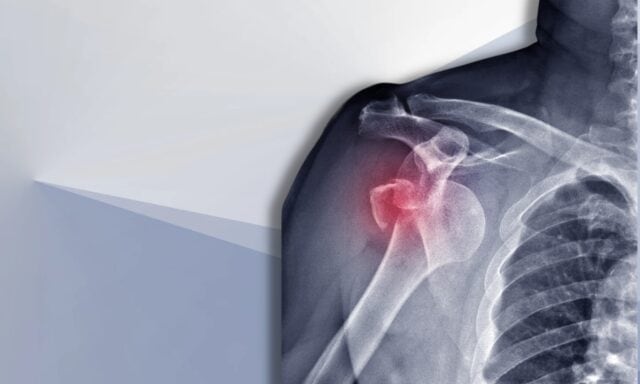

I denne episoden skal vi snakke om alt som er ustabilt i skuldrene. Du vil lære mer om Stanmore-klassifiseringen og strukturelle skader etter dislokasjoner. Vi vil diskutere den typiske pasienten med skulderinstabilitet og hvordan en undersøkelsesprosess ser ut. Vi vil komme inn på muskelaktiveringsmønstre, kirurgi og hvordan fysioterapeutisk behandling av en pasient med skulderinstabilitet eventuelt kan se ut. Så sørg for å høre hele episoden!